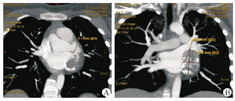

最终有6例患儿纳入本次研究。其中,男5例,女1例;年龄为(148.7±29.0)个月,范围在106~203个月;体重为(47.9±15.5)kg,范围在27.5~76 kg。所有患儿均明确诊断为川崎病,术前长期接受药物治疗,治疗药物包括丙种球蛋白、糖皮质激素、阿司匹林、华法林、双嘧达莫等,治疗平均时长为5.7年,范围在3个月至10年。6例患儿病程中出现不同程度心功能不全表现(1例心功能Ⅱ级,4例心功能Ⅲ级及1例心功能Ⅳ级),临床症状包括胸闷气促、活动耐量下降等,5例患儿心电图检查提示ST段改变。心脏彩色超声及心脏CT检查结果提示冠状动脉进行性扩张,形成巨大动脉瘤(图1),部分瘤内生成血栓影响冠状动脉血液流速。心脏彩色超声CAA诊断标准:CAE是指心外膜下冠状动脉的局限性或弥漫性扩张,超过邻近正常血管的1.5倍,若大于2倍则称为CAA或瘤样扩张[2]。本次研究中4例为单发巨大CAA,2例为多发串珠样CAA;单侧CAA1例,双侧CAA5例;其中3例合并瘤内血栓,1例合并室壁瘤。